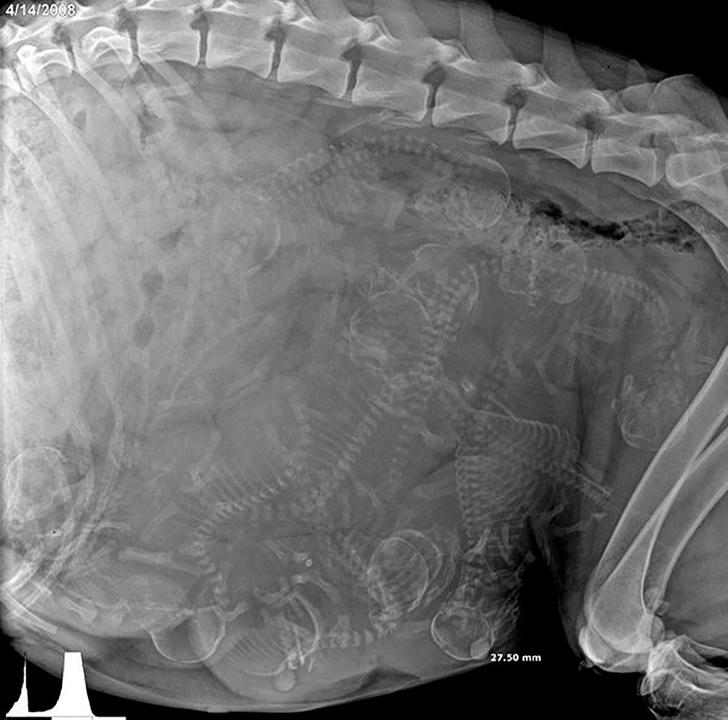

Рентгенівський знімок вагітної собаки